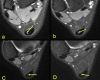

The aim of the study was to check if the subtendons of the Achilles tendon can be identified in vivo on MRI in the midportion of the tendon. The relation of the plantaris tendon to the Achilles tendon was also examined. A retrospective study of 200 MRI of ankle joints including the Achilles tendon was conducted. Statistical analysis of the correlation between the possibility of identifying the subtendons and the side, gender, presence of the central soleus tendon and plantaris tendon variation was performed. The inter-observer agreement between two reviewers in their evaluation of the subtendons was assessed using kappa statistics. The subtendon from the lateral head of the gastrocnemius muscle was identified in 65% (k = 0.63) and was located in the anterior part of the Achilles tendon. The subtendon from the soleus muscle was recognized in 12% (k = 0.75) comprising anterior part of the tendon. In 6% the subtendon from the medial head of the gastrocnemius muscle was identified (k = 0.58). The central soleus tendon was identified in 85% of cases. Statistical analysis shows the weak correlation of the presence of the central soleus tendon and the possibility of identifying the subtendon from the soleus muscle. The plantaris tendon was directly related to the insertion of the Achilles tendon in 42.5%. Identification of the subtendons of the Achilles tendon on MRI is challenging, and most often it is only possible to find the subtendon of the lateral head of the gastrocnemius muscle.